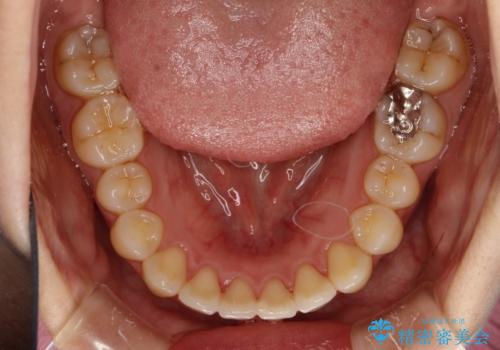

インビザラインによるガタつきの矯正治療 シンプル・短期間

- 非抜歯、IPR+拡大によるマウスピース矯正を計画した。

一見前歯のガタつきだけのように見えても、そのガタつきの根本的な原因が奥歯の位置であったりすると、マウスピースの枚数がそれなりに多くなり、治療に時間がかかることもあります。